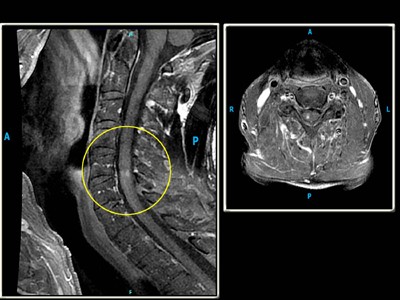

Bệnh do giun đầu gai trên động vật có thể rất nghiêm trọng trong diễn tiến bệnh, thậm chí cóthể dẫn đến tử vong do các biến chứng, ngược lại thể bệnh trên người, đặc biệt đối với loài Gnathostoma spinigerum, hình thái lâm sàng biểu hiện nhiều nhất là hội chứng ban trườn, ấu trùng di chuyển dưới da và thể bệnh ở phủ tạng hiếm gặp hơn. Khi biểu hiện không điển hình dễ chẩn đoán nhầm với một số bệnh nội khoa và da liễu khác. Thể thần kinh của giun đầu gai biểu hiện lâm sàng với các triệu chứng và biến chứng (viêm não màng não, viêm rễ tủy, viêm màng não, xuất huyết nhu mô não hoặc dưới nhện, nhồi máu não,…) khó có thể định phân giữa các bệnh lý nội thần kinh khác nếu thầy thuốc lâm sàng không nghĩ đến, nên dễ bỏ sót bệnh và tử vong là có thể xảy ra. Di chứng có thể lên đến 8-25% nếu chẩn đoán và xử trí bệnh không kịp thời(2,5).

Bảng 5. Đặc điểm lâm sàng của ấu trùng giun đầu gai ở tạng, cơ quan khác

TT | Đặc điểm nhóm nghiên cứu (n= 77) | Thời điểm bắt đầu |

1 | Cơ quan tiêu hóa - Đau bụng không rõ ràng - Đau vùng thượng vị - mũi ức - Đau vùng hạ sườn (P) - Rối loạn tiêu hóa, phân sệt à lỏng (đợt) - Đau dạng co thắt đường mật từng cơn | 16 (20.78%) 4 (5.2%) 2 (2.6%) 2 (2.6%) 3 (3.9%) |

2 | Cơ quan hô hấp - Đau ngực - Khó thở - Khạc đờm có máu | 4 (5.2%) 1 (1.3%) 1 (1.3%) |

3 | Cơ quan thị giác Phù di chuyển ở mi mắt trên Nhìn mờ kiểu song thị | 2 (2.6%) 1 (1.3%) |

Ấu trùng gây thượng tổn tại một số cơ quan như tiêu hóa, hô hấp và thị giác với nhiều phổ lâm sàng khác nhau.